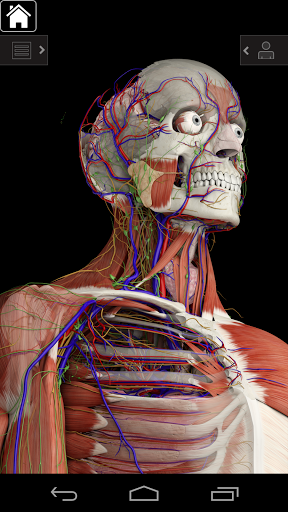

Essential Anatomy 3 représente la toute dernière technologie 3D révolutionnaire et un design innovant. Un moteur graphique 3D de pointe, construit sur mesure par 3D4Medical à partir de zéro, alimente un modèle anatomique très détaillé et fournit des graphiques de qualité exceptionnelle qu'aucun autre concurrent ne peut atteindre.

L'application représente une approche unique à l'apprentissage de l'anatomie générale. Les graphismes sont inégalés et rendent l'apprentissage, grâce à l'utilisation de contenu informatif et de fonctionnalités innovantes, une expérience riche et engageante.

NOUVELLE TECHNOLOGIE 3D

Essential Anatomy 3 est réactif, visuellement magnifique et sans effort. L'application est entièrement 3D, ce qui signifie que vous pouvez voir n'importe quelle structure anatomique dans l'isolement, ainsi que de n'importe quel angle.

---- Plus de 4000 structures anatomiques très détaillées